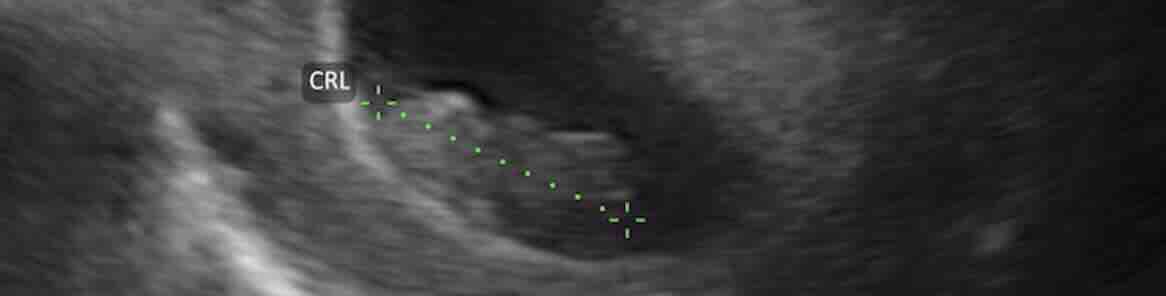

Toplam süre:

???? Ortalama 3–5 dakika

HSG ne zaman çekilir, en ideal gün hangisi?

HSG için en uygun dönem adet bittikten sonraki 6–11. günler arasıdır. Bu aralıkta gebelik ihtimali düşüktür, rahim içi daha net görülür ve enfeksiyon riski daha azdır. Düzensiz kanaması olanlarda doktorunuz kişiye özel gün planlaması yapar.